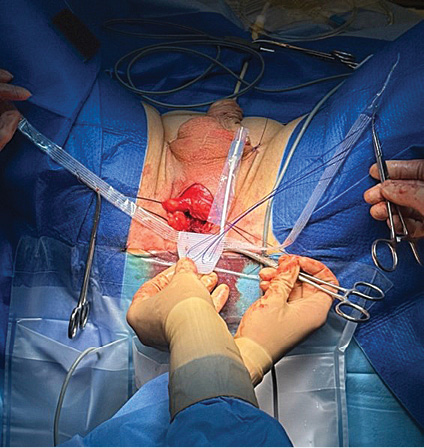

Pacientas ištirtas: atliktas kosulio testas, šlapimo sulaikymo testas, šlapimo tyrimai, urogenitalinės sistemos echoskopija, liekamasis šlapimas, urofloumetrograma, uretrocistoskopija, pilvo ir dubens organų kompiuterinė tomografija. Tyrimų rezultatai parodė, kad nėra infekcijos, šlaplės striktūrų ir liekamojo šlapimo, PSA (prostatos specifinis antigenas serume) tyrimo rezultatas – 0,01 ng/ml, onkologinio proceso plitimo nerasta. Uretrocistoskopijos metu nustatyta, kad sfinkterio vieta neužsidaro, repozicinis testas teigiamas. Įvertinus tyrimų rezultatus ir nustačius vidutinio laipsnio šlapimo nelaikymą, 2023-03-25 pacientui implantuota reguliuojamoji ATOMS sistema (1 pav.).

ATOMS sistema turi dvi dalis: pagalvėlę ir specialų rezervuarą, pagamintą iš titano. Šios dvi dalys tarpusavyje sujungtos. Operacijos metu atliekamas tik vienas pjūvis. Implanto pagalvėlė, duriant specialiomis adatomis, per tarpvietės pjūvį ir per užtvarinę angą pakišama po šlaple. Rezervuaras punktuojamas specialia adata (port needle 20 G/0,9 mm), pagalvėlė užpildoma fiziologiniu tirpalu, kuris patenka į implanto pagalvėlę, esančią po šlaple, ir pagalvėlė priglunda prie šlaplės. Rezervuaras implantuojamas po kapšelio oda. Pagalvėlės pripildymą galima reguliuoti tiek operacijos metu, tiek atlikus operaciją. Reguliuojant šią sistemą po operacijos, chirurginės intervencijos nereikia. Pakanka punktuoti specialia adata per kapšelio odą rezervuarą ir suleisti arba išsiurbti reikiamą skysčio kiekį [8, 9].

Operacija atlikta taikant bendrąją nejautrą, specialiomis adatomis per užtvarinę angą implantuojant pošlaplinio raiščio pagalvėlę po šlaple ir rezervuarą po kapšelio oda (2–5 pav.). Operacija praėjo be komplikacijų.

2 pav. Pošlaplinis implantas

3 pav. Implantas ir rezervuaras

4 pav. Implanto užpildymas punktuojant specialia adata

5 pav. Po kapšelio oda užčiuopiamas rezervuaras